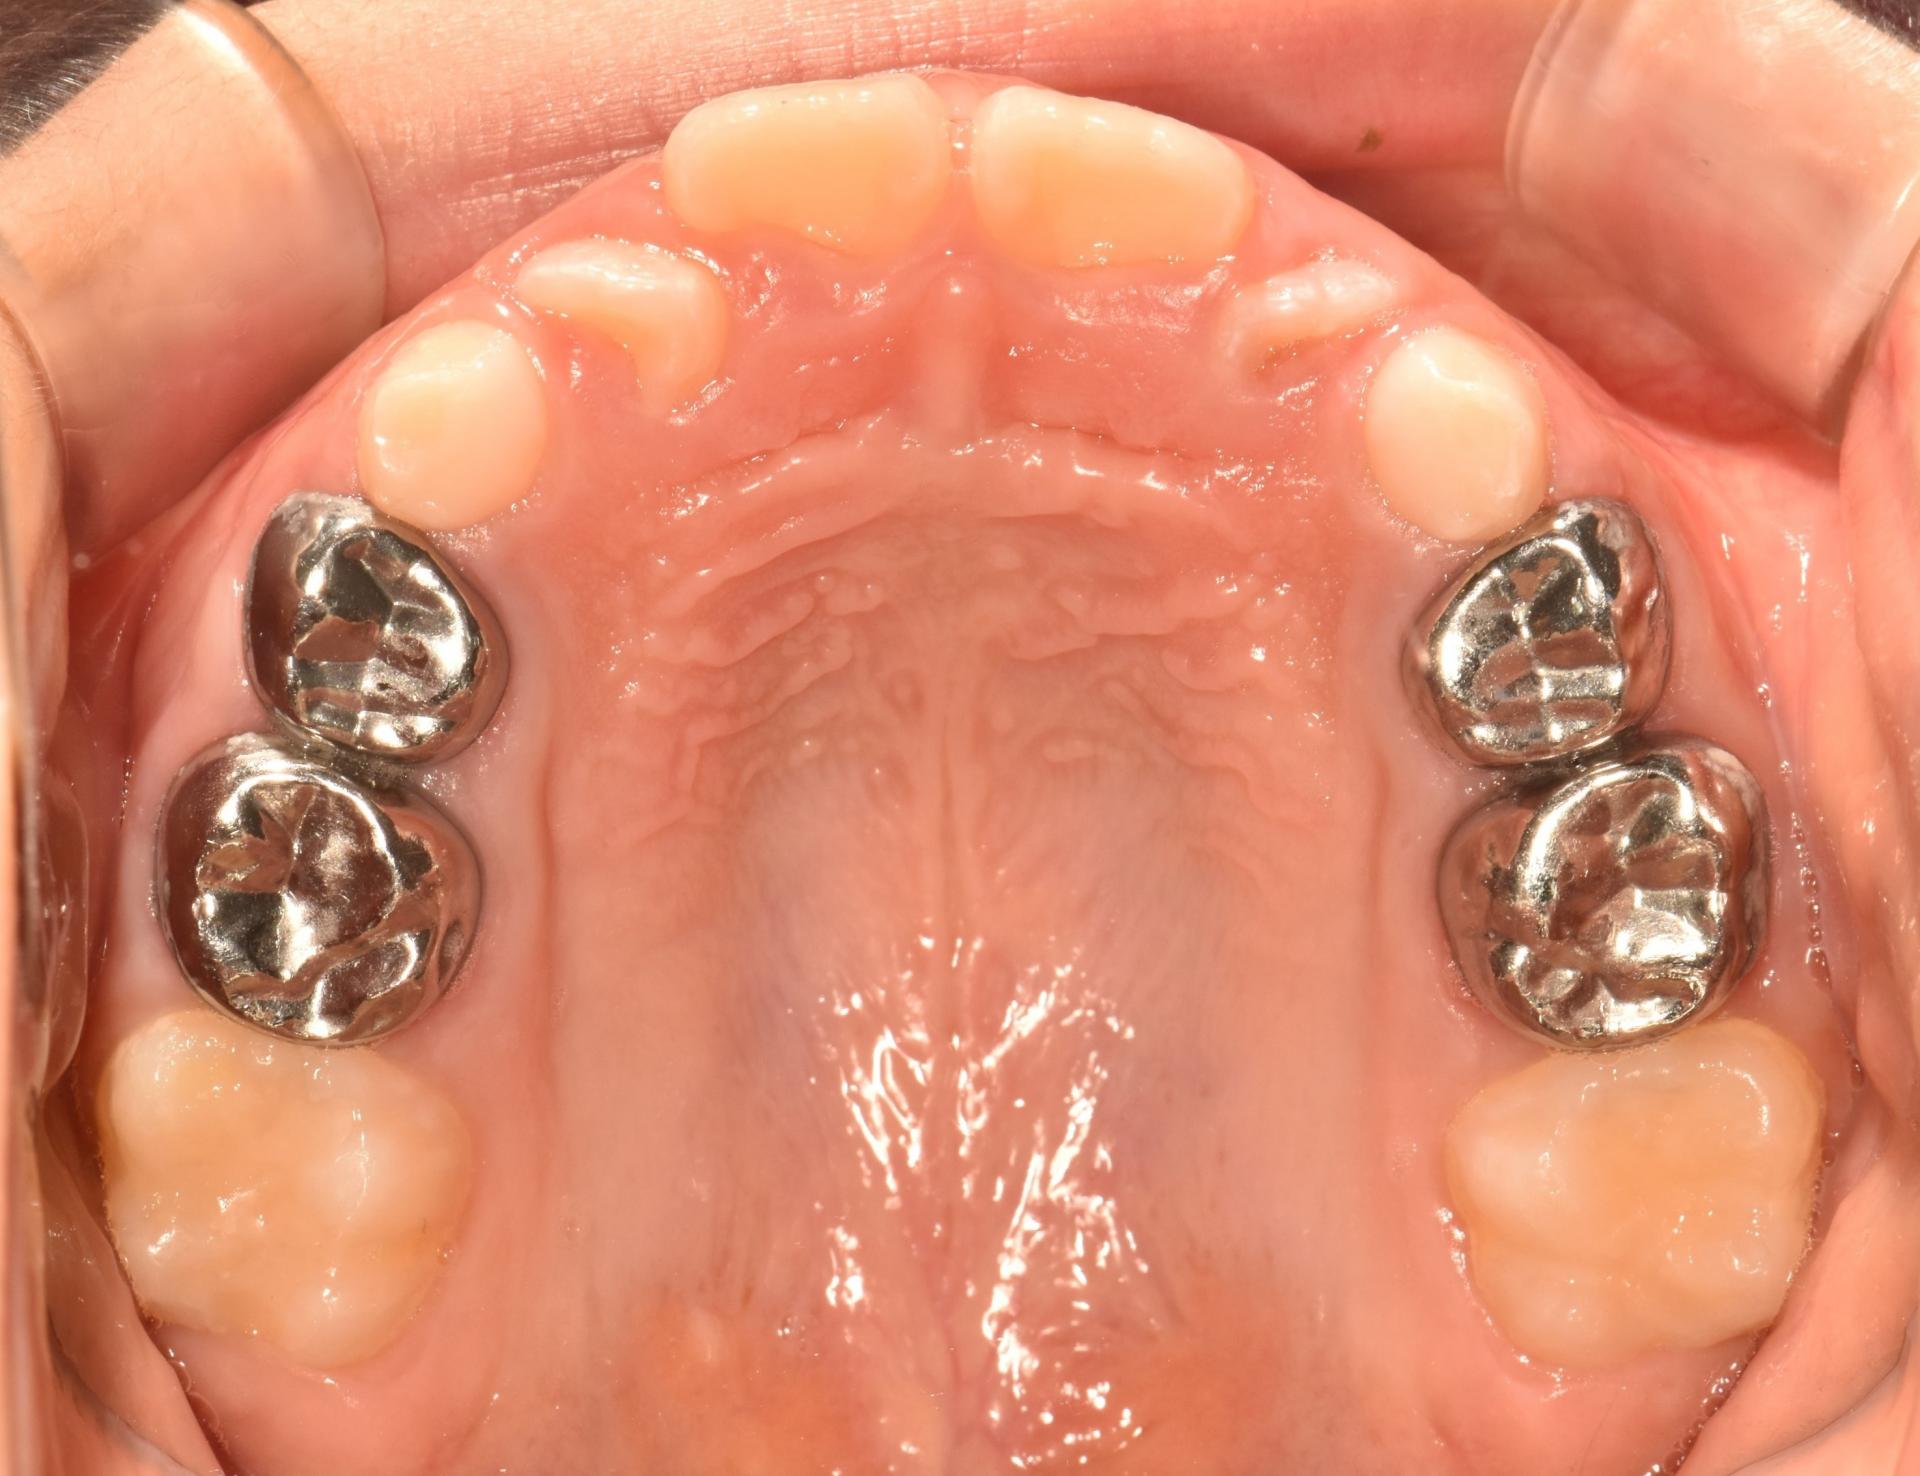

예전부터 많이 하던 교정으로, 악궁확장장치(뺐다꼈다 하는 장치)로 악궁을 넓혀 공간을 만들고 삐뚤빼뚤한 치아는 브라켓 철사교정으로 예쁘게 해주었습니다.